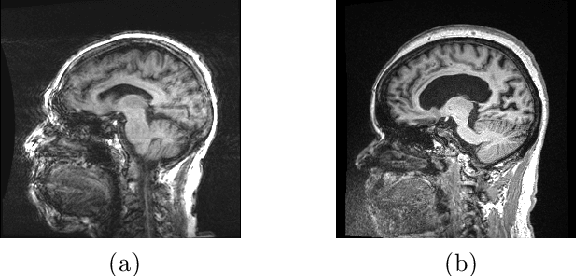

Abstract:Quality control (QC) of MR images is essential to ensure that downstream analyses such as segmentation can be performed successfully. Currently, QC is predominantly performed visually and subjectively, at significant time and operator cost. We aim to automate the process using a probabilistic network that estimates segmentation uncertainty through a heteroscedastic noise model, providing a measure of task-specific quality. By augmenting training images with k-space artefacts, we propose a novel CNN architecture to decouple sources of uncertainty related to the task and different k-space artefacts in a self-supervised manner. This enables the prediction of separate uncertainties for different types of data degradation. While the uncertainty predictions reflect the presence and severity of artefacts, the network provides more robust and generalisable segmentation predictions given the quality of the data. We show that models trained with artefact augmentation provide informative measures of uncertainty on both simulated artefacts and problematic real-world images identified by human raters, both qualitatively and quantitatively in the form of error bars on volume measurements. Relating artefact uncertainty to segmentation Dice scores, we observe that our uncertainty predictions provide a better estimate of MRI quality from the point of view of the task (gray matter segmentation) compared to commonly used metrics of quality including signal-to-noise ratio (SNR) and contrast-to-noise ratio (CNR), hence providing a real-time quality metric indicative of segmentation quality.

Abstract:Quality control (QC) in medical image analysis is time-consuming and laborious, leading to increased interest in automated methods. However, what is deemed suitable quality for algorithmic processing may be different from human-perceived measures of visual quality. In this work, we pose MR image quality assessment from an image reconstruction perspective. We train Bayesian CNNs using a heteroscedastic uncertainty model to recover clean images from noisy data, providing measures of uncertainty over the predictions. This framework enables us to divide data corruption into learnable and non-learnable components and leads us to interpret the predictive uncertainty as an estimation of the achievable recovery of an image. Thus, we argue that quality control for visual assessment cannot be equated to quality control for algorithmic processing. We validate this statement in a multi-task experiment combining artefact recovery with uncertainty prediction and grey matter segmentation. Recognising this distinction between visual and algorithmic quality has the impact that, depending on the downstream task, less data can be excluded based on ``visual quality" reasons alone.